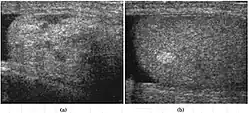

Teratoma Although teratoma is the second most common testicular tumor in children, it affects all age groups. Mature teratoma in children is often benign, but teratoma in adults, regardless of age, should be considered malignant. Teratomas are composed of all three germ cell layers, i.e. endoderm, mesoderm and ectoderm. At ultrasound, teratomas generally form well-circumscribed complex masses. Echogenic foci representing calcification, cartilage, immature bone and fibrosis are commonly seen [Fig. 5]. Cysts are also a common feature and depending on the contents of the cysts i.e. serous, mucoid or keratinous fluid, it may present as anechoic or complex structure [Fig. 6].

Fig. 5. Teratoma. A plaque-like calcification with acoustic shadow is seen in the testis. -

Fig. 6. Mature cystic teratoma. (a) Composite Image. Mature cystic teratoma in a 29-year-old man. Longitudinal sonography image of the right testis shows a multilocular cystic mass. (b) Mature cystic teratoma in a 6-year-old boy. Longitudinal sonography of the right testis shows a cystic mass containing calcification with no obvious acoustic shadow.